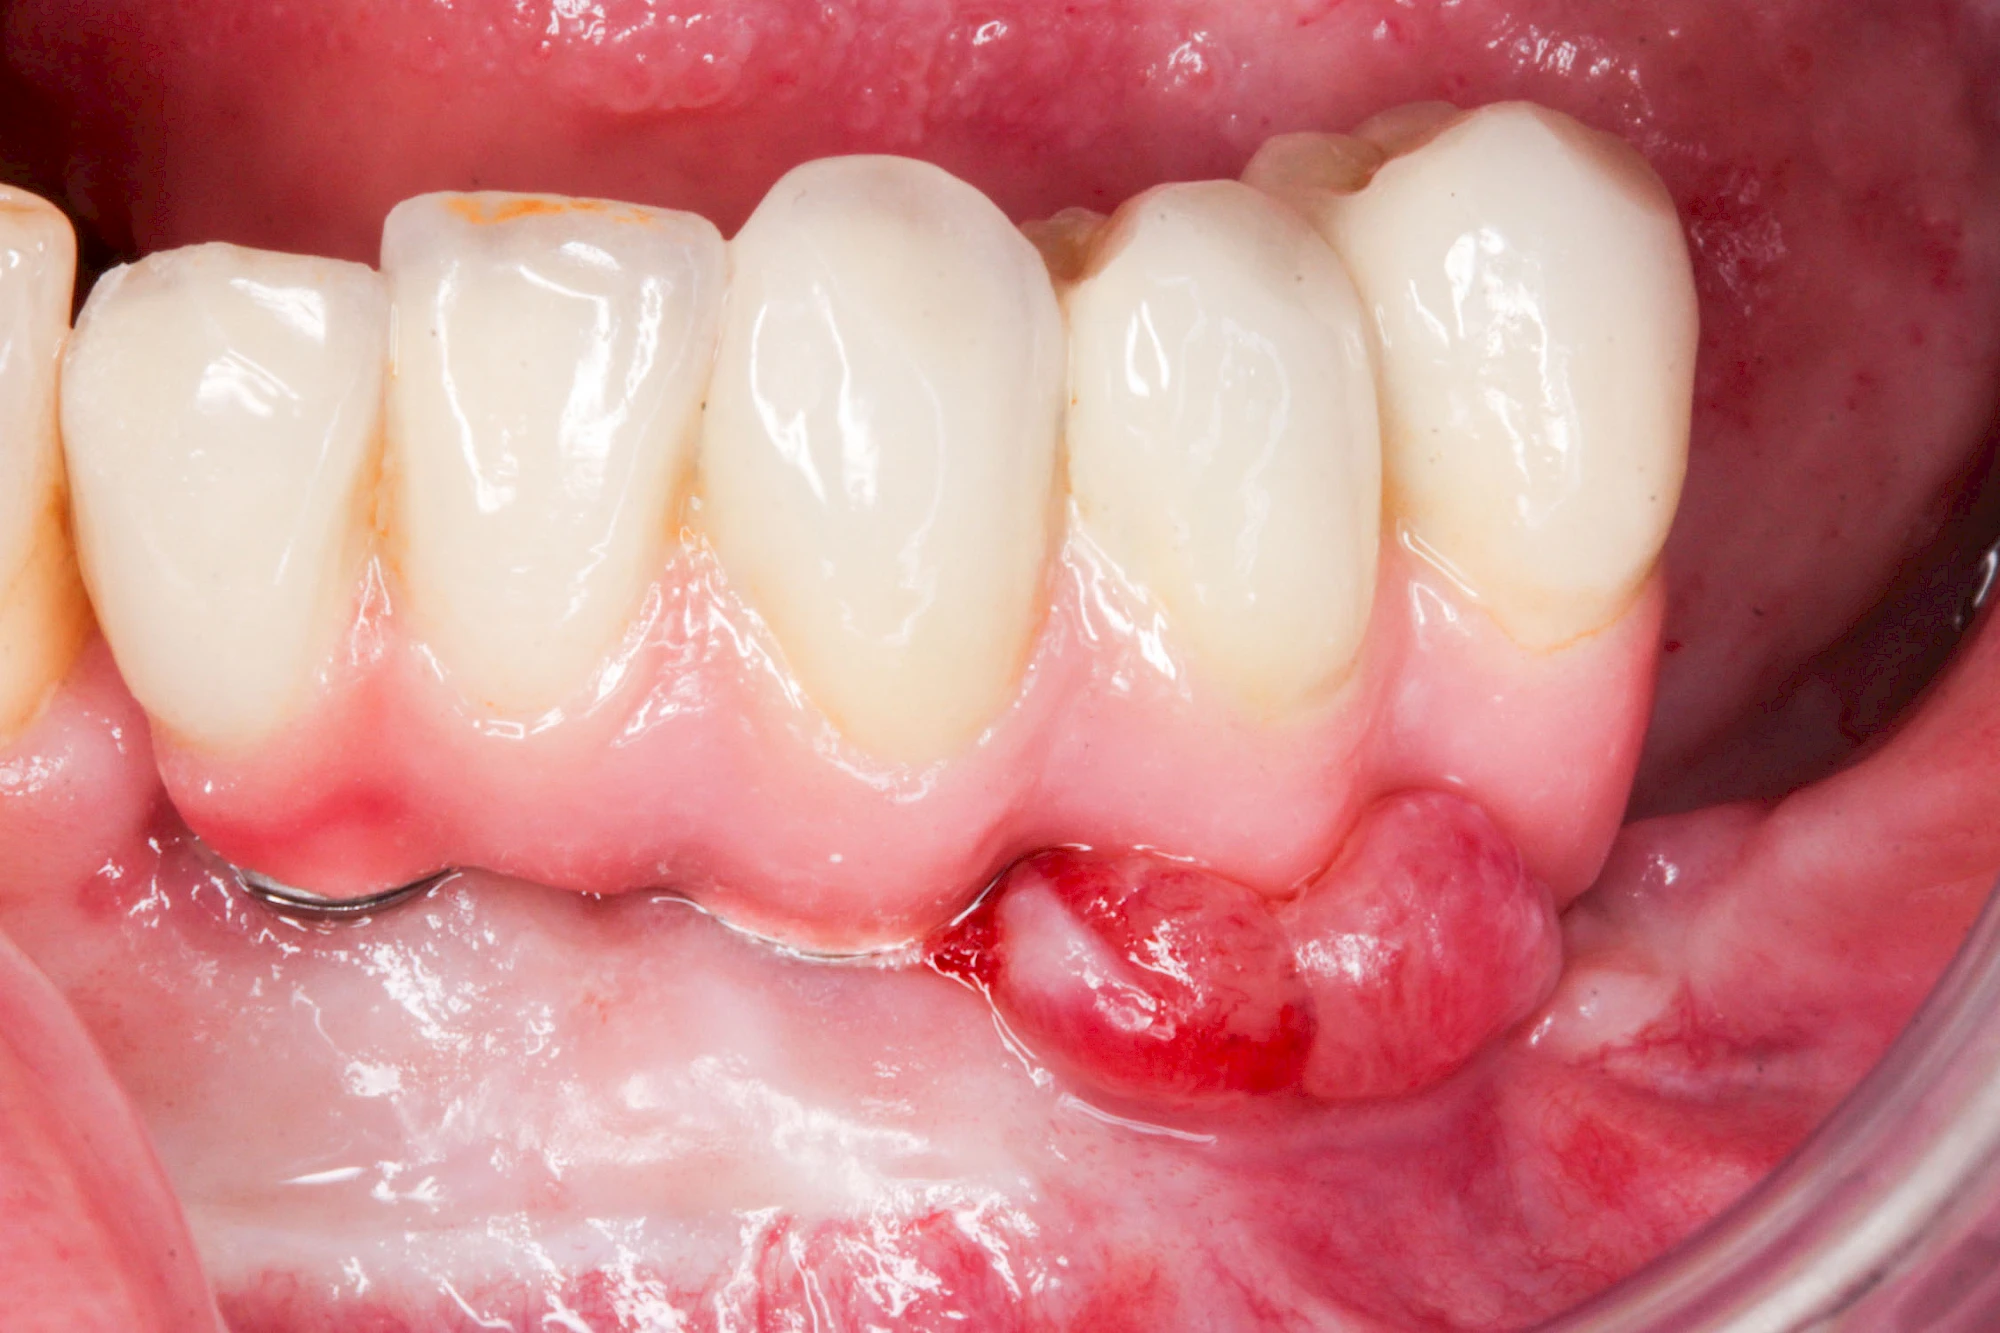

Ist zunächst nur das Zahnfleisch von der Entzündung betroffen, spricht man von Gingivitis. Später, wenn auch der Knochen um die Zähne herum entzündet ist, spricht man von einer Parodontitis. Bei der Parodontitis wird der Knochen nach und nach abgebaut und das Zahnfleisch zieht sich zurück. Die Zahnhälse und Zahnwurzeloberflächen liegen mehr und mehr frei. Die Zähne werden zunehmend lockerer und fallen schließlich aus.

Sonderform: Wucherung

Epulis

Diese Vermehrung von Bindegewebe im Bereich des Zahnfleisches kann auf folgende Ursachen zurückgeführt werden:

- Nebenwirkung von Medikamenten: Immunsuppressiva (Cyclosporin A), Antihypertonika (Kalziumantagonisten/Kalziumkanalblocker: Nifedipin, Amlodipin sowie Diltiazem, Verapamil) und Antiepileptika (Phenytoin)

- Hormonschwankung im Rahmen der Schwangerschaft (Schwangerschaftsepulis)

Diese Vermehrung von Bindegewebe in einem frei gewordenen Raum ist eine Sonderform der Anpassungsreaktion menschlicher Zellen und wird als Vakatwucherung bezeichnet.

Früher wurden im Unterkiefer mitunter Brücken zum Ersatz fehlender Zähne als sogenannte "Schwebebrücken" gestaltet. Die Idee dabei war, dass man die Brücke insgesamt besser reinigen kann. Allerdings war das für die Patienten mitunter irritierend für die Zunge und vor allem beim Essen gewöhnungsbedürftig. Teilweise haben sich hier reaktiv Vakatwucherungen der Kieferkammschleimhaut gebildet und den Raum unter der Brücke wieder verschlossen.